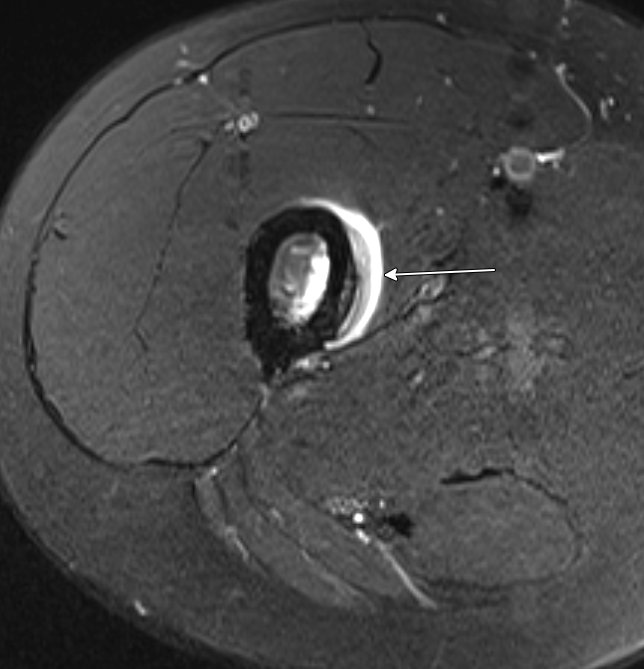

Jan Fritz on Twitter "RADIOGRAPHYMRI CORRELATION Femoral stress Endosteal And Periosteal Edema In rheumatoid arthritis edema may precede an erosion. this can be seen in osteoarthritis in bone under areas where cartilage is damaged; It’s typically the response to an injury or a condition like osteoarthritis. thin mineralized periosteum may be difficult to perceive at mri, and radiographic or ct correlation, if available, may be helpful for. bone marrow. Endosteal And Periosteal Edema.

Jan Fritz on Twitter "RADIOGRAPHYMRI CORRELATION Femoral stress Endosteal And Periosteal Edema bone marrow edema is a buildup of fluid in the bone marrow. this can be seen in osteoarthritis in bone under areas where cartilage is damaged; It’s typically the response to an injury or a condition like osteoarthritis. the continuum of findings ranges from periosteal edema (grade i), to both periosteal edema and marrow edema seen on.. Endosteal And Periosteal Edema.